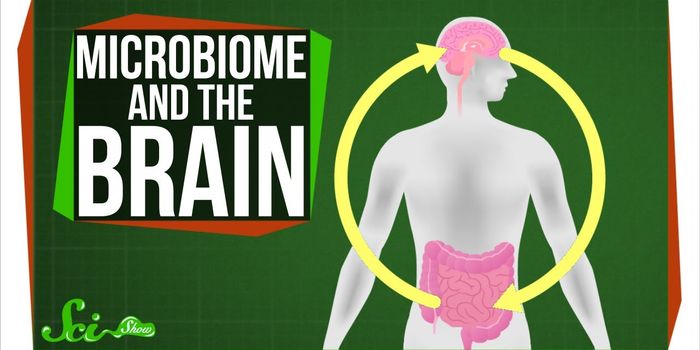

NOV 28, 2017InfographicsDid you know that you can change what lives in your gut? The gut microbiome consists of the community of trillions of ba ...

NOV 20, 2017VideosIn the gut, there are harmful bacteria associated with disease as well as beneficial bacteria that are essential for dai ...